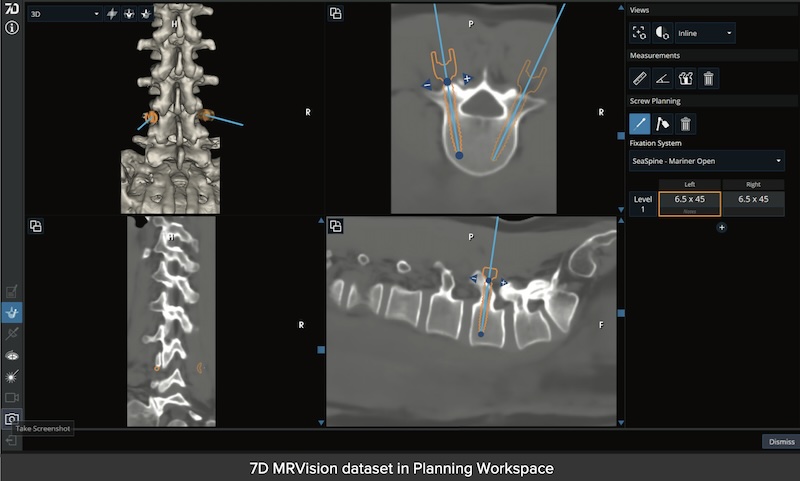

• MRIVision Module:

• Utilizes a specialized MRI sequence acquired preoperatively to produce a synthetic CT image which can be used to perform intraoperative FLASH for instant registration.

• Makes a completely radiation free process